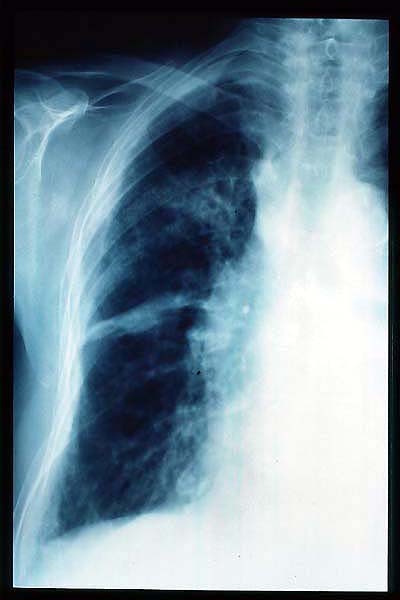

TBC pulmonar antigua